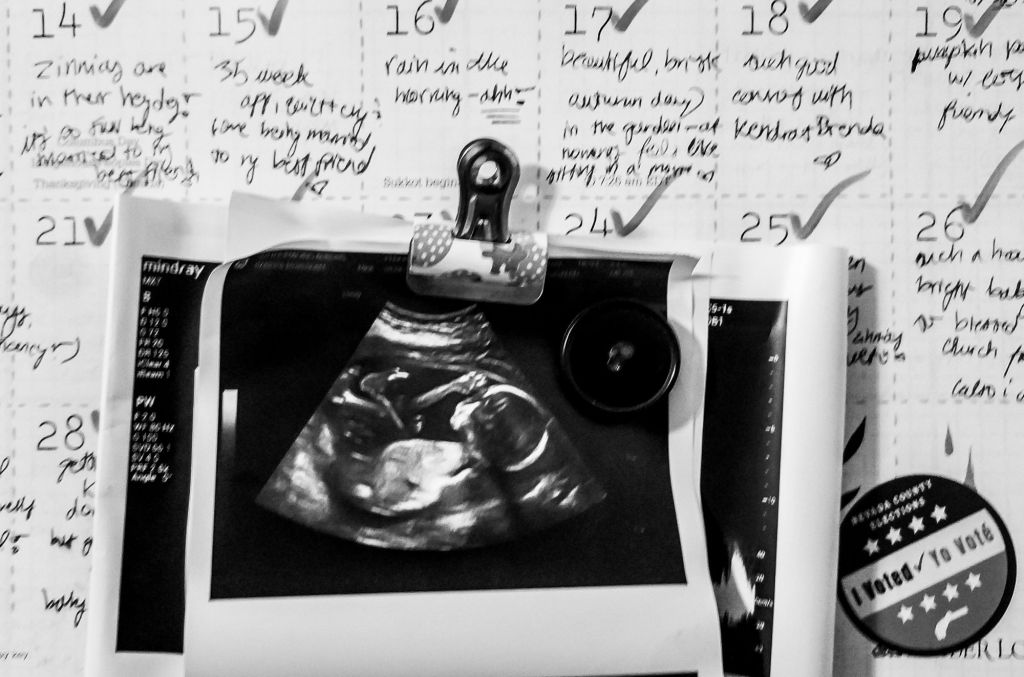

feel the baby kick

within,

and I can sense

her enthusiasm

for life outside

the womb.

(I’m excited for you

too.)